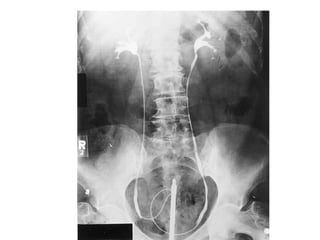

The kidneys can be injured by blunt or penetrating trauma, requiring timely medical evaluation. The kidneys are normally protected by back muscles but can be damaged by severe impacts or objects piercing the skin. Blunt trauma may cause bruising while penetrating injuries like gunshots can enter elsewhere and travel to the kidneys. Most kidney injuries are minor but evaluation with imaging tests like ultrasound or CT scans helps classify the injury and guide management, which may include rest, antibiotics, surgery, or nephrectomy in more severe cases.